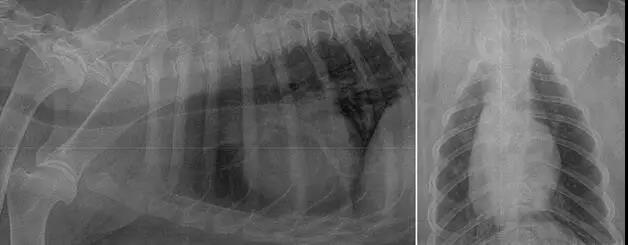

X光檢查:胸腔右側(cè)位片 X光檢查:胸部正位片